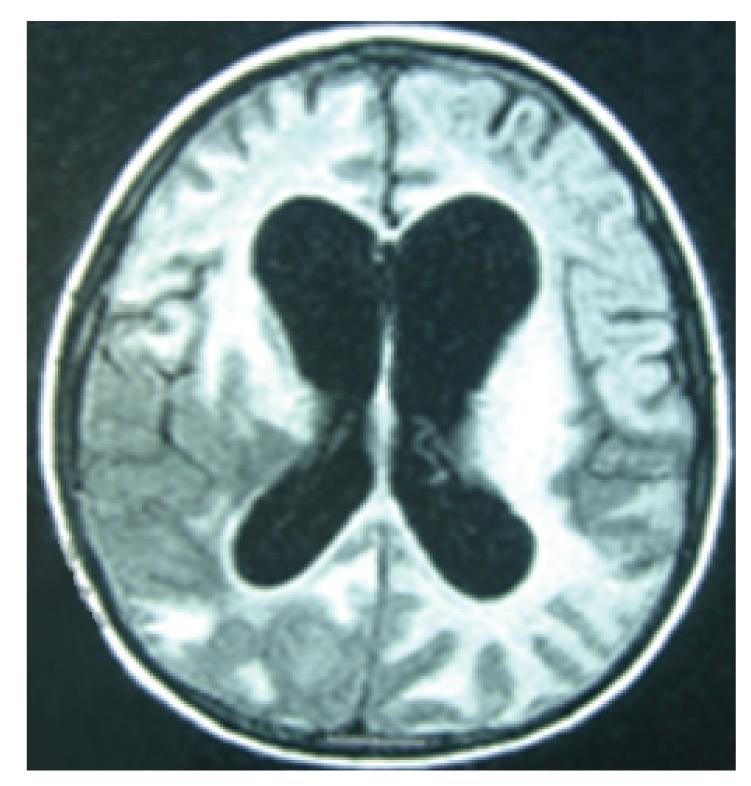

We report a case of a perinatally HIV-infected patient aged 9 years, who presented with right-sided hemiplegia. His initial CD4 T-cell was of 0.21% (4 cells/muL) and plasma HIV RNA virus of 185 976 copies/mL (log 5.27). Plasma and CSF samples were subsequently positive for JCV. Twelve days after the initiation of highly active antiretroviral therapy (HAART), the MRI showed progressive white matter lesions with asymmetrical deep and subcortical white matter lesions over the left frontotemporoparietal region and the right frontal lobe. Immune Reconstitution Inflammatory Syndrome (IRIS) was suspected, and the patient was treated with methylprednisolone. His clinical symptoms worsened and despite therapy the patient deteriorated.

我们报告了一例9岁的围产期感染艾滋病毒的患者,该患者出现右侧偏瘫。其初始CD4 T细胞为0.21%(4个细胞/微升),血浆艾滋病毒RNA病毒载量为185976拷贝/毫升(对数5.27)。随后血浆和脑脊液样本检测JC病毒呈阳性。在开始高效抗逆转录病毒治疗(HAART)12天后,MRI显示白质病变进展,左侧额颞顶叶区域和右侧额叶出现不对称的深部和皮质下白质病变。怀疑为免疫重建炎症综合征(IRIS),患者接受甲泼尼龙治疗。其临床症状恶化,尽管进行了治疗,患者仍病情恶化。